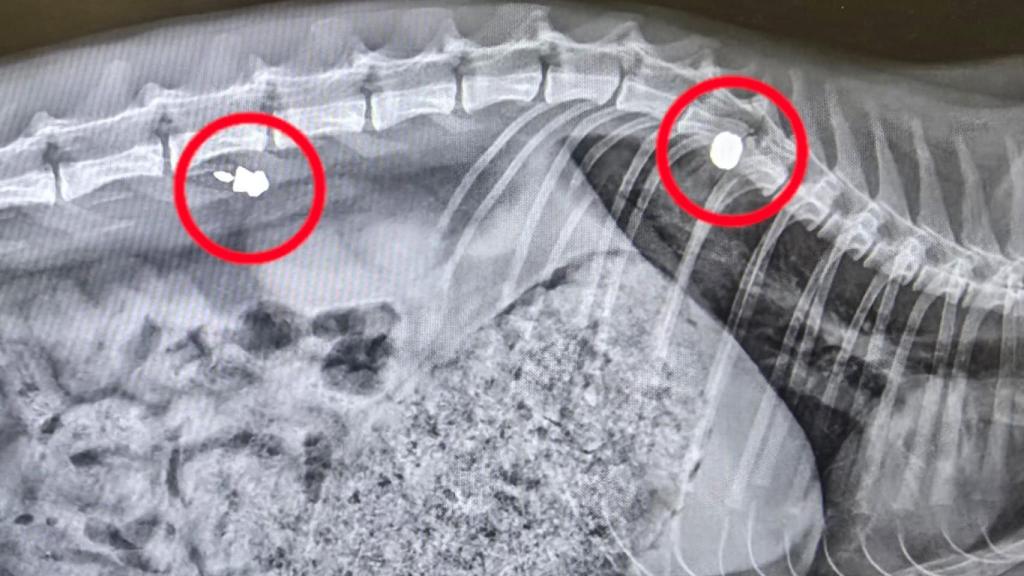

Las pruebas veterinarias confirmaron que la gata tenía dos impactos de balines, uno antiguo y otro reciente. Este último es el que le ha causado la parálisis.

El proyectil impactó en la columna vertebral y comprimió la médula. "El disparo tenía que ser bastante cerca", sostiene Jallais, basándose en la opinión de los especialistas.

La gata ha sido intervenida para extraer el plomo y fragmentos óseos. La operación ha salido bien, pero el pronóstico sigue siendo grave.

El último de los proyectiles impactó muy cerca de la médula, dejándola paralítica.